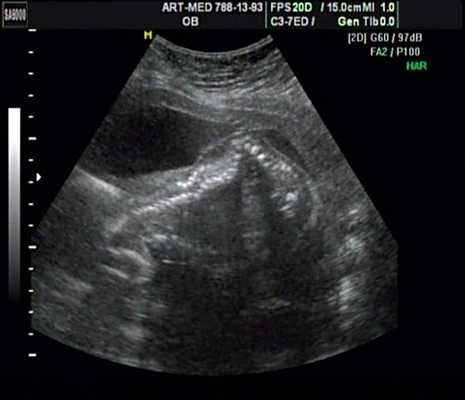

Характерными особенностями выраженной объемной перегрузки правого желудочка являются дилатация желудочка, при которой толщина миокарда не превышает верхней границы нормы, увеличение правого предсердия, парадоксальный характер движения межжелудочковой перегородки и увеличение амплитуды движения трикуспидального клапана (рис. 2, 3).

Рис. 2. Длинная ось сердца. Объемная перегрузка правого желудочка при дефекте межпредсердной перегородки. Объем сброса крови превышает 200% МОС. Отмечается выраженная дилатация правого желудочка.

Рис. 3. Объемная перегрузка правого желудочка при дефекте межпредсердной перегородки. В- и М-сканирование. Стрелкой показан парадоксальный характер движения межжелудочковой перегородки.